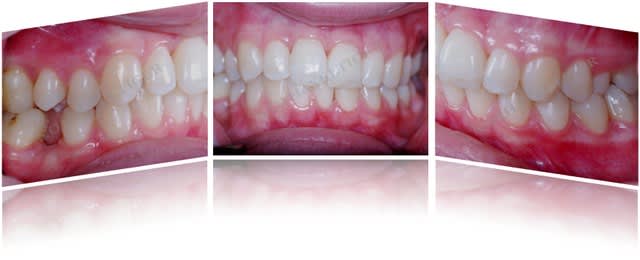

Cas 2 (parodontite aggressive sur une jeune fille de 13 ans)

Photos initiales c6c2bg - Eugenol

Bilan initial nhvmno - Eugenol

Photos  1an drrxtl - Eugenol

Comparaison bilan rx bix6qa - Eugenol

Bilan de sondage  1 an muiwyr - Eugenol